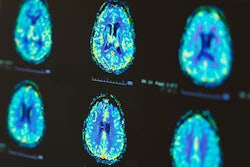

The updated version provides new CE-marked functionalities for displaying and analyzing nuclear medicine images across modalities, including PET/CT, SPECT/CT, PET/MR, and RTDOSE, the Stockholm-based firm said in a statement.

The new Hermia functionalities include computer-assisted organ segmentation, the Dmax tool for quantifying lesion spread in disseminated disease, and a split tool for manual separation of adjacent lesions or physiological uptake.